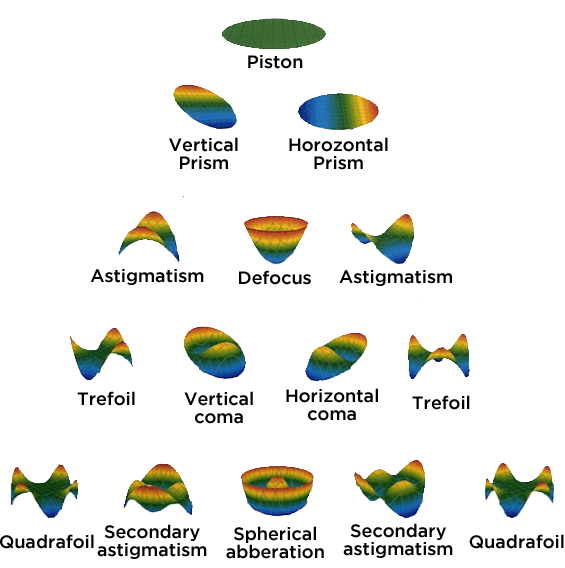

Why do stars sometimes “twinkle” in the sky? Atmospheric turbulence: the light that comes from the star gets distorted by particles in the atmosphere. It is the same with light entering the eye: it passes through the cornea and the lens (the “optics”) and is focussed on the retina (the neurological part) where the light is converted into nerve impulses that are transmitted up into the brain. Imperfections – particularly in the cornea, which is responsible of 80% of the eye’s focusing power – can then distort the light in many different ways. Some wholesale imperfections in the system (like myopia, hyperopia and astigmatism) are quite obvious, and are termed “lower-order aberrations”, whereas others tend to be only noticeable at night, and have terms like “trefoil, coma and spherical aberration”, and are referred to as “higher order aberrations” – HOAs. The more complicated the shape that the light gets distorted into, the higher the order of aberration (Figure 1).

Figure 1. Common aberration shapes created when a “wavefront” of light passes through eyes with imperfect vision. A theoretically perfect eye (top) is represented by an aberration-free flat plane known as a “piston”. Each row further down from the top represents an increasingly “higher order” (i.e. more complex) aberration.

Many clinics have corneal topographers that can also perform a corneal aberration analysis, and they work by determining anterior and posterior corneal elevation data (the shape of the top and bottom of the cornea). This is combined with a technique called ray-tracing, and the resulting data is represented as something called the “Zernike polynomial” – as seen above in Figure 1.

The investigators compared the third- and fourth-order Zernike polynomial data each instrument produced with a 6.0 mm pupil, including:

- trefoil at 0°,

- trefoil at 30°,

- vertical coma,

- horizontal coma,

- spherical aberration, and

- total cornea root mean square (RMS),